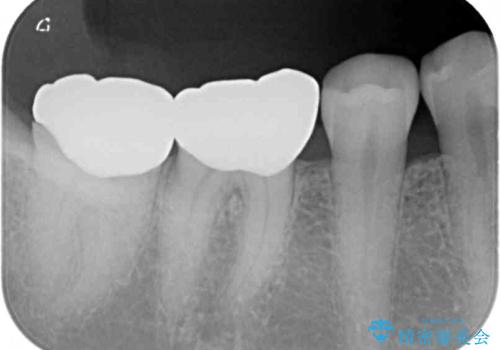

- 以前、職場近くで夜遅くまで治療していた医院で装着した奥歯のクラウンが、壊れたり汚れたりしていることを気にして来院された患者様です。

以前は安価であったことからハイブリッドクラウンを選択されたそうですが、すぐに具合が悪くなってしまったので、今回はオールセラミッククラウンにて補綴治療を行うこととしました。

咬合力が強く、土台の歯の高さが低かったたため、より高強度のフルジルコニアクラウンにて補綴治療を行いました。